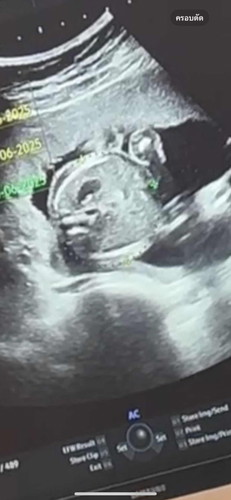

ตอน 20 สัปดาห์ค่ะ

แม่คะสอบถามหน่อยค่ะอันนี้ใช่หน้าน้องไหมคะ🙏🥰

น่าจะเป็นหัวน้องนะคะคุณแม่

ขนาดศรีษะค่ะแม่